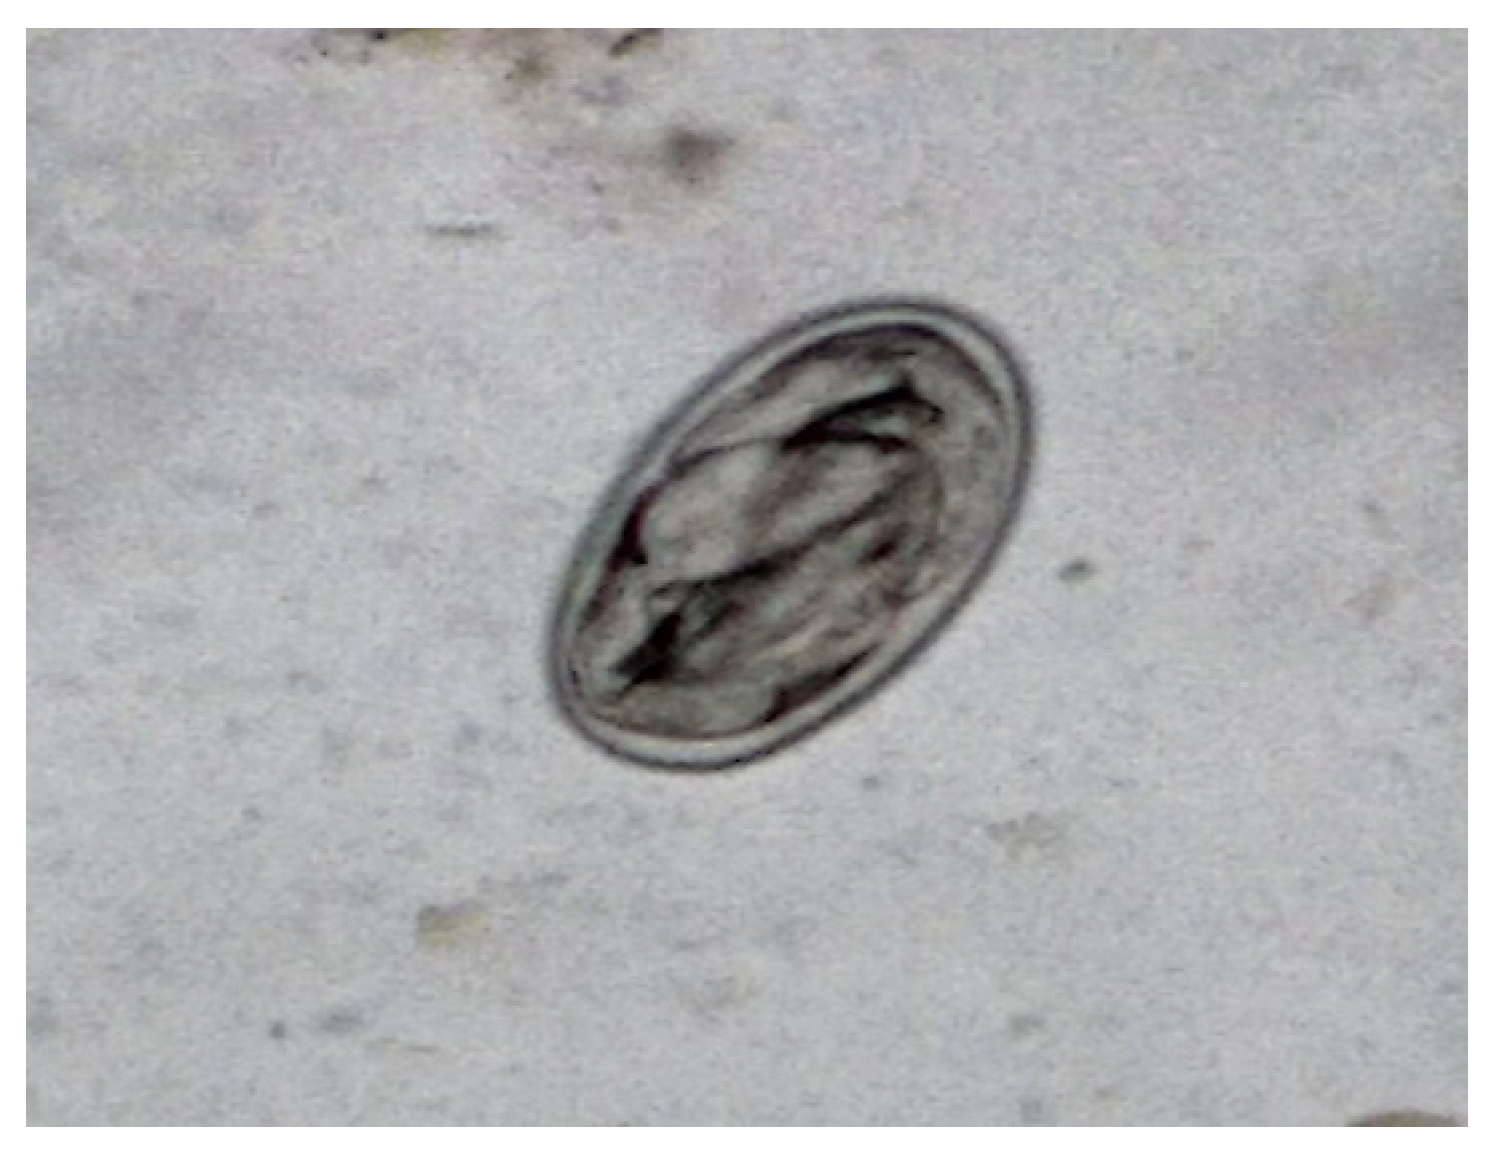

During the observation in the ATU, it was verified that the animal presented apathy, cachexia, ruffled feathers, dirty feathers around the cloaca with dry feces, vomiting, and dyspnea, spending most of the time with eyes closed. During this period, a sudden change in the ambient temperature was also observed, as it was a period of intense rainfall with an average rainfall of 366 mm and a minimum average temperature of 23ºC and a maximum of 28ºC. The importance of cold environments for birds is emphasized, as they tend to increase their metabolism to maintain body temperature. The copro-parasitological exams carried out using the direct fresh method and the centrifuge-flotation technique detected many eggs of the Diplotriaenoidea superfamily (Figure 1).

Figure 1. Egg of the Diplotriaenoidea superfamily identified by the direct fresh method.